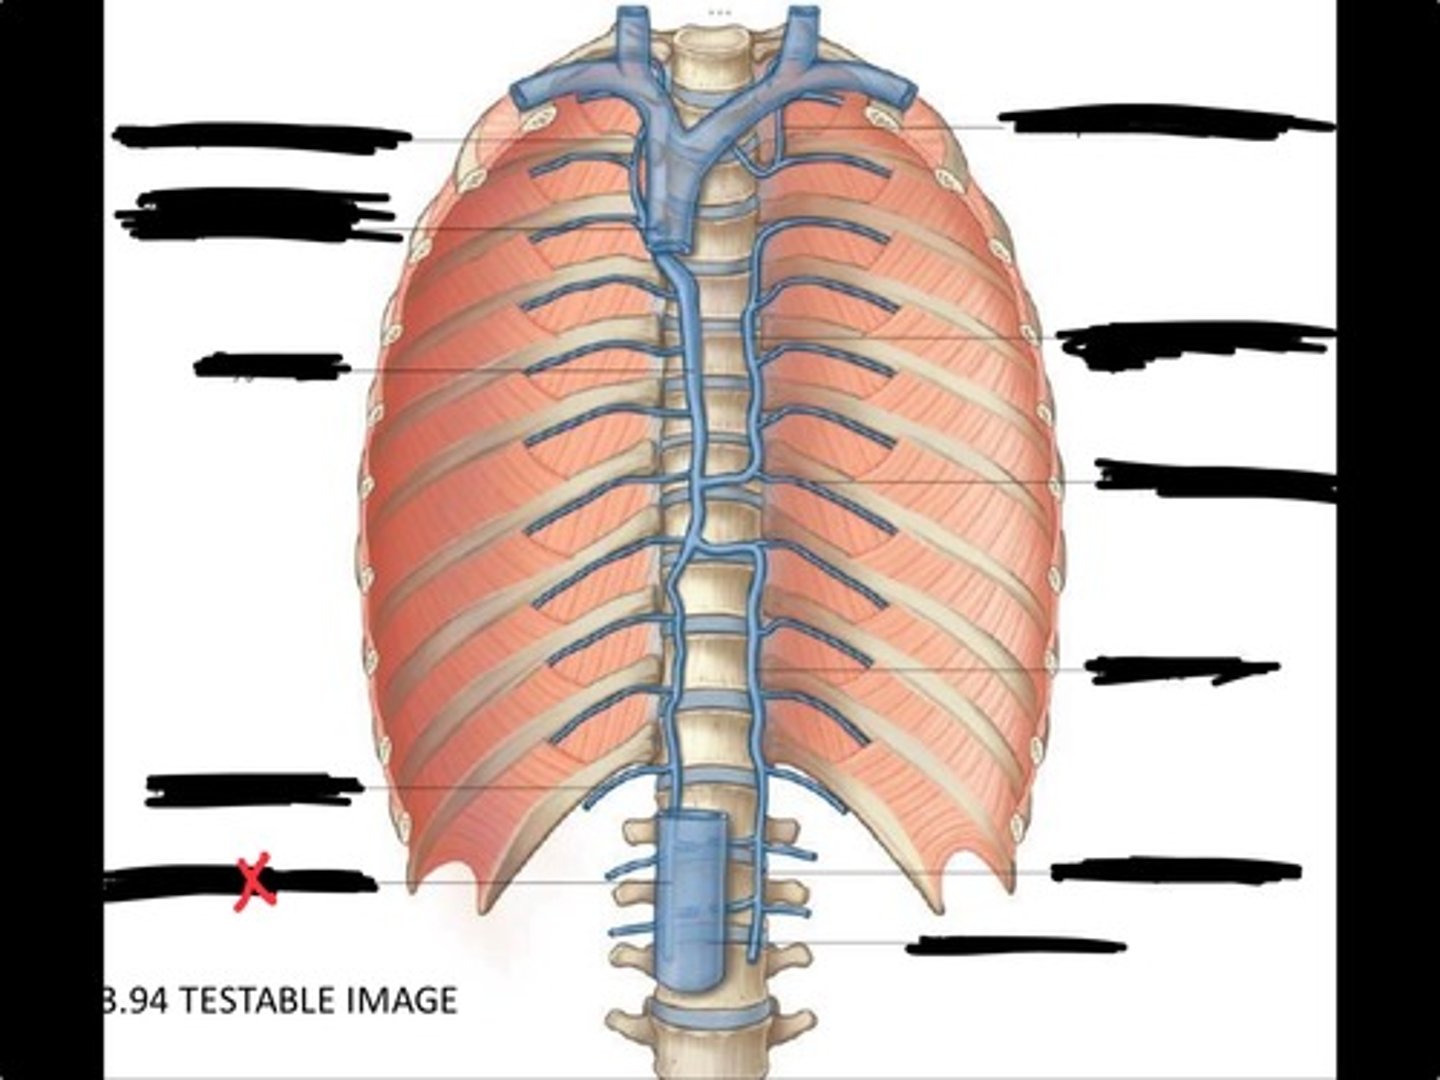

Right ascending lumbar vein

Right subcostal vein

Azygos vein

Opening of the azygos vein into superior vena cava

Right superior intercostal vein

Left superior intercostal vein

Accessory hemiazygos vein

Posterior intercostal vein

Hemiazygous vein

Ascending lumbar vein